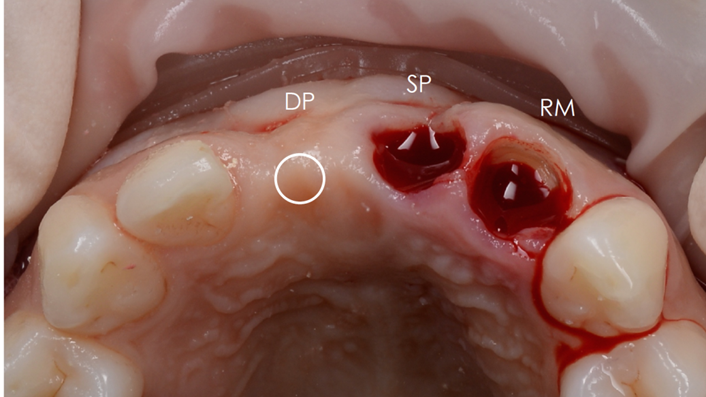

Clinical case: 3.0 mm MiNi implants placement at #12, #22

- Courtesy of Dr. Achraf Souayah, Tunise -

Keywords

Anterior esthetics, MiNi, flap elevation, minimally invasive technique, soft tissue management, esthetic zone, Dr. Achraf Souayah, anterior aesthetics, aesthetic, aesthetics, esthetic, #12, #22

Products:

MiNi implant system